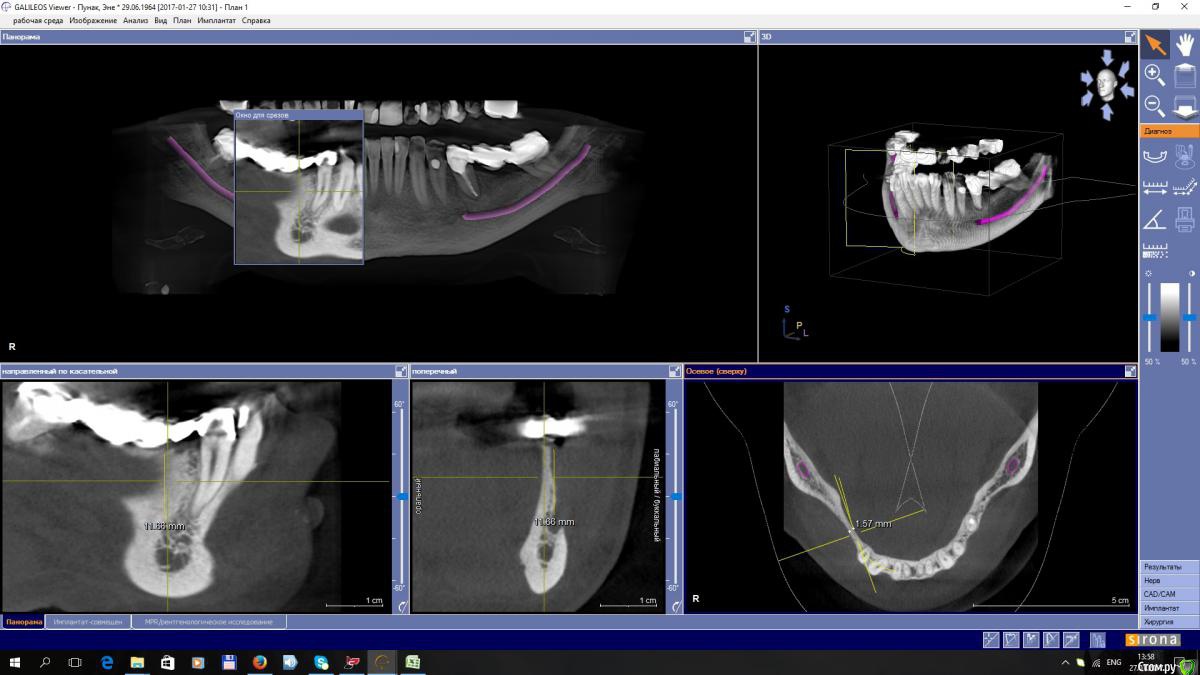

EEcho Опубликовано 30 января, 2017 Автор Поделиться Опубликовано 30 января, 2017 покажите срезы дальше(дистальнее) может целесообразно провести аугментацию дистально, возможно там ситуация получше... и сделать медиальную консоль на 5ый зуб.Срезы в области 45, 46, 47,48, Ссылка на комментарий

EEcho Опубликовано 30 января, 2017 Автор Поделиться Опубликовано 30 января, 2017 А какими методиками владеете?Наверное всеми ныне существующими. костной пластикой занимаюсь порядка 8-ми лет, но с таким ножевидным гребнем встречаюсь в первые. сплошная кортикалка, кровоснабжение гребня желает быть лучше, есть мысль разрез сделать на 3 мм ниже гребня язычно, без отслойки лоскута с язычной, и мембрану бить в открывшуюся кость. но есть сомнения. не могу прогнозировать отдаленный результат. Ссылка на комментарий